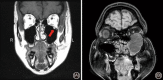

Methods: Two latex-injected cadaveric specimens were utilized to perform surgical dissections to demonstrate different approaches to the MS. The procedures were documented with macroscopic images and endoscopic pictures.

Results: Dissections were performed to approach the MS medially (endoscopic maxillary antrostomy and ethmoidectomy), anteriorly (Caldwell-Luc), superiorly (transconjunctival/transorbital approach), inferiorly (transpalatal approach), and posterolaterally (preauricular hemicoronal approach).